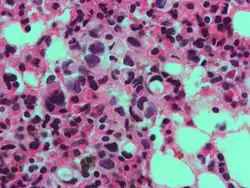

В гистологии перстневидными клетками называют клетки с большой вакуолью. Перстневидные клетки являются злокачественными и, как правило, обнаруживаются в карциномах. Перстневидные клетки наиболее часто выявляются при раке желудка, однако могут возникать в любом типе тканей, включая простату, мочевой пузырь, жёлчный пузырь, молочные железы, толстый кишечник, строму яичников и тестикулы.